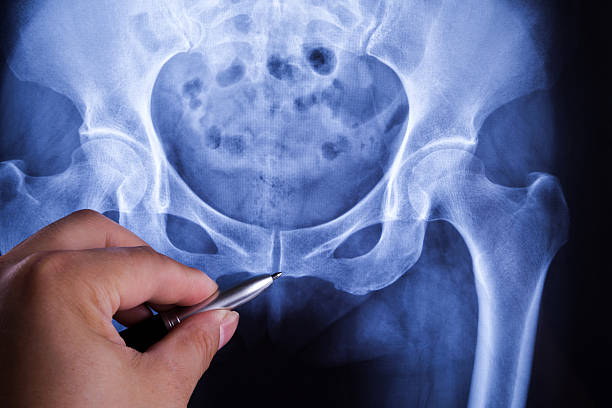

골반의 위쪽, 장골 뼈 주변 부위가 아플 때 주로 중둔근이 문제가 됩니다. 이 근육은 장골능을 감싸고 있는데, 골반이 전방으로 비틀렸을 때 특히 앞으로 이동할 때 이 부위에서 통증이 발생할 수 있습니다. 또한, 흉추나 요추 부분에 문제가 있는 경우에도 이곳에서 통증이 나타날 수 있습니다.

골반 통증 원인 - 엉덩이 중간

엉덩이 중간 부위에 통증이 나타나면 대둔근의 깊은 부분 또는 좌골신경 주변에 문제가 있을 가능성이 높습니다. 골반이 비틀릴 때 대둔근이 약해지면서 이 부위에 통증이 올 수 있습니다. 또한, 좌골신경 압박이나 디스크 문제로 인해도 엉덩이 중간 부위가 아프게 느껴질 수 있습니다.

골반 통증 원인 - 엉덩이 아래쪽

아래쪽 엉덩이 부위가 아프다면 주로 대둔근의 하부 섬유가 문제가 됩니다. 골반이 비틀릴 때 이 부위도 영향을 받아 아프게 될 수 있습니다. 오래 앉아 있는 경우 대둔근이 바닥에 닿게 되면 더 많이 아프게 될 수 있으므로 장시간 앉는 것을 피하고 대둔근을 강화하는 운동을 해야 합니다.

골반 통증 원인 - 골반 바깥쪽

골반 바깥쪽 위쪽 부위가 아프면 대퇴근막장 또는 골반 주변 근육의 문제일 가능성이 높습니다. 골반이 전망으로 비틀릴 때 대퇴근막장이 긴장하며 엉덩이 바깥 부분이 뻐근하게 아프게 됩니다. 고관절을 오래 굴곡시키는 자세나 앉는 자세를 피하고, 관련 근육의 스트레칭을 통해 개선할 수 있습니다.

골반 통증 원인 - 골반 가운데

가운데로 오면 천골과 장골 사이의 천골 관절이 주로 문제가 됩니다. 골반이 뒤로 빠질 때 이 관절 부분에서 통증이 나타날 수 있으며, 이를 바로 잡아주는 치료가 필요합니다. 또한, 천골 주변에 기립근과 인대가 연결되어 있어 이 부위에도 통증이 나타날 수 있으므로 관련 스트레칭을 통해 개선할 수 있습니다.